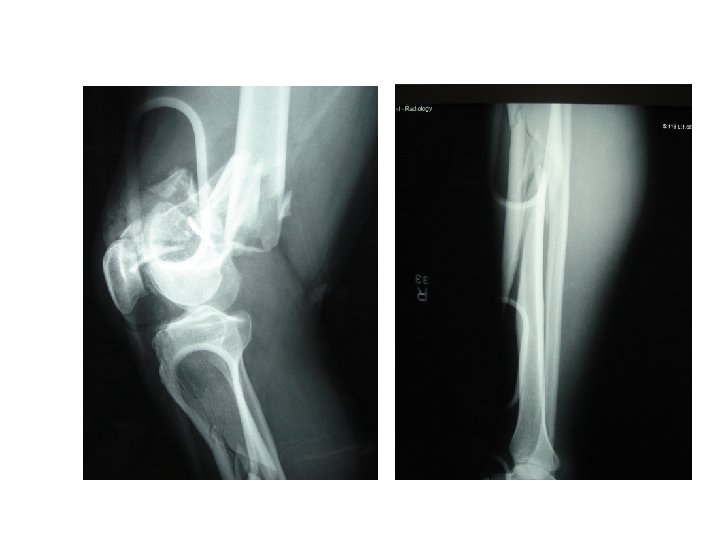

Diagnosis • PE • • • Deformity, wounds Bleeding, hematoma Pulses Signs of ischemia Neurological examination Posterior knee dislocation – Popliteal a. injury up to 25%

Combined vascular and orthopedic injury • Restore perfusion 1 st ! • Definitive repair – stable, minimally displaced Fx • TIVS – complex, displaced Fx – TIVS Bone manipulation definitive repair – avoid major stress on vascular anastomosis

Factors associated with amputation • • • Extensive soft-tissue injuries Associated skeletal trauma Knee dislocations Prolonged ischemic times Nerve injury High extremity AIS 1)Yahya et al. ANZ J Surg, 2005 2) NTDB J Vasc Surg. 2006 Jul; 44(1): 94 -100